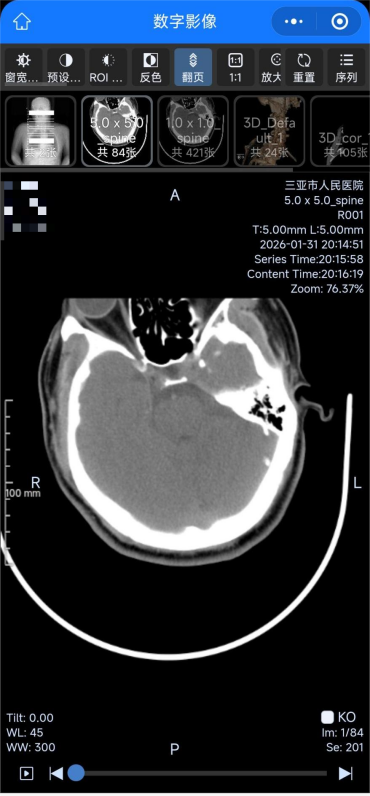

此次升级后,患者在医院完成X线、CT、磁共振等检查,影像数据会实时上传至云端服务器,患者无需在现场等候胶片打印,通过扫描报告单、预约单二维码,或进入医院官方微信公众号,即可在手机、平板等终端便捷调阅、下载、分享完整影像数据及诊断报告。

患者检查后可在手机上查阅高清影像图片。